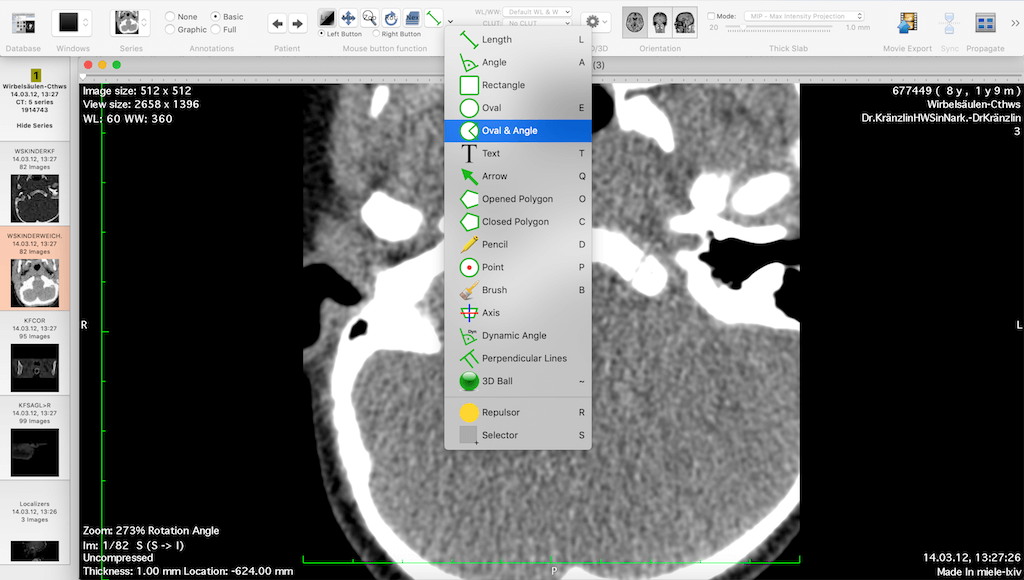

Miele LXIV is a free DICOM viewer for Mac operating systems. It has advanced features including MPR, MIP, volume rendering, and image fusion. In addition, it also allows 4D viewing of cardiac CTs. It is PACS-integrated and can send and receive files from a PACS database.

| 16. | Miele LXIV | Mac OS X | PACS integrated | Y | Y | Y | Y | 50 MB | Intel processor | Free to use |